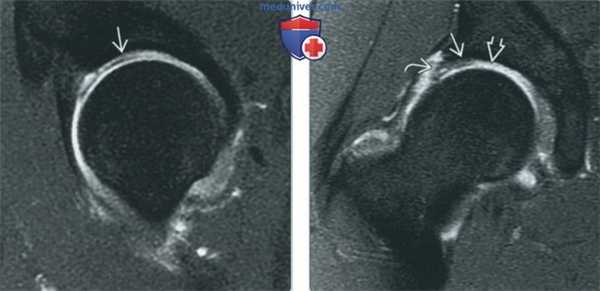

(Слева) МР-артрография в режиме Т1ВИ, коронарный срез, пациент с жалобами на рецидив болевого синдрома после артроскопической операции по поводу БВИ: определяется вогнутость в месте проведения остеохондро-пластики, что не является признаком заболевания. Источником боли, вероятно, служит отслоение суставной губы.

(Справа) МР-артрография в режиме Т1ВИ, коронарный срез: отмечается неправильное расположение дефекта после остеохондропластики, так как резекция латеральной суставной поверхности была выполнена слишком высоко. Отмечается затек контрастного препарата в уменьшенную суставную губу, что обусловлено неэффективностью ее восстановления. (Слева) Артроскопия, состояние после остеохондропластики: выполняется дебридмент - удаление поврежденных фрагментов в области перехода головки бедренной кости в шейку. Вверху определяется обрывистый контур головки бедренной кости. Для доступа к шейке суставная капсула была рассечена.